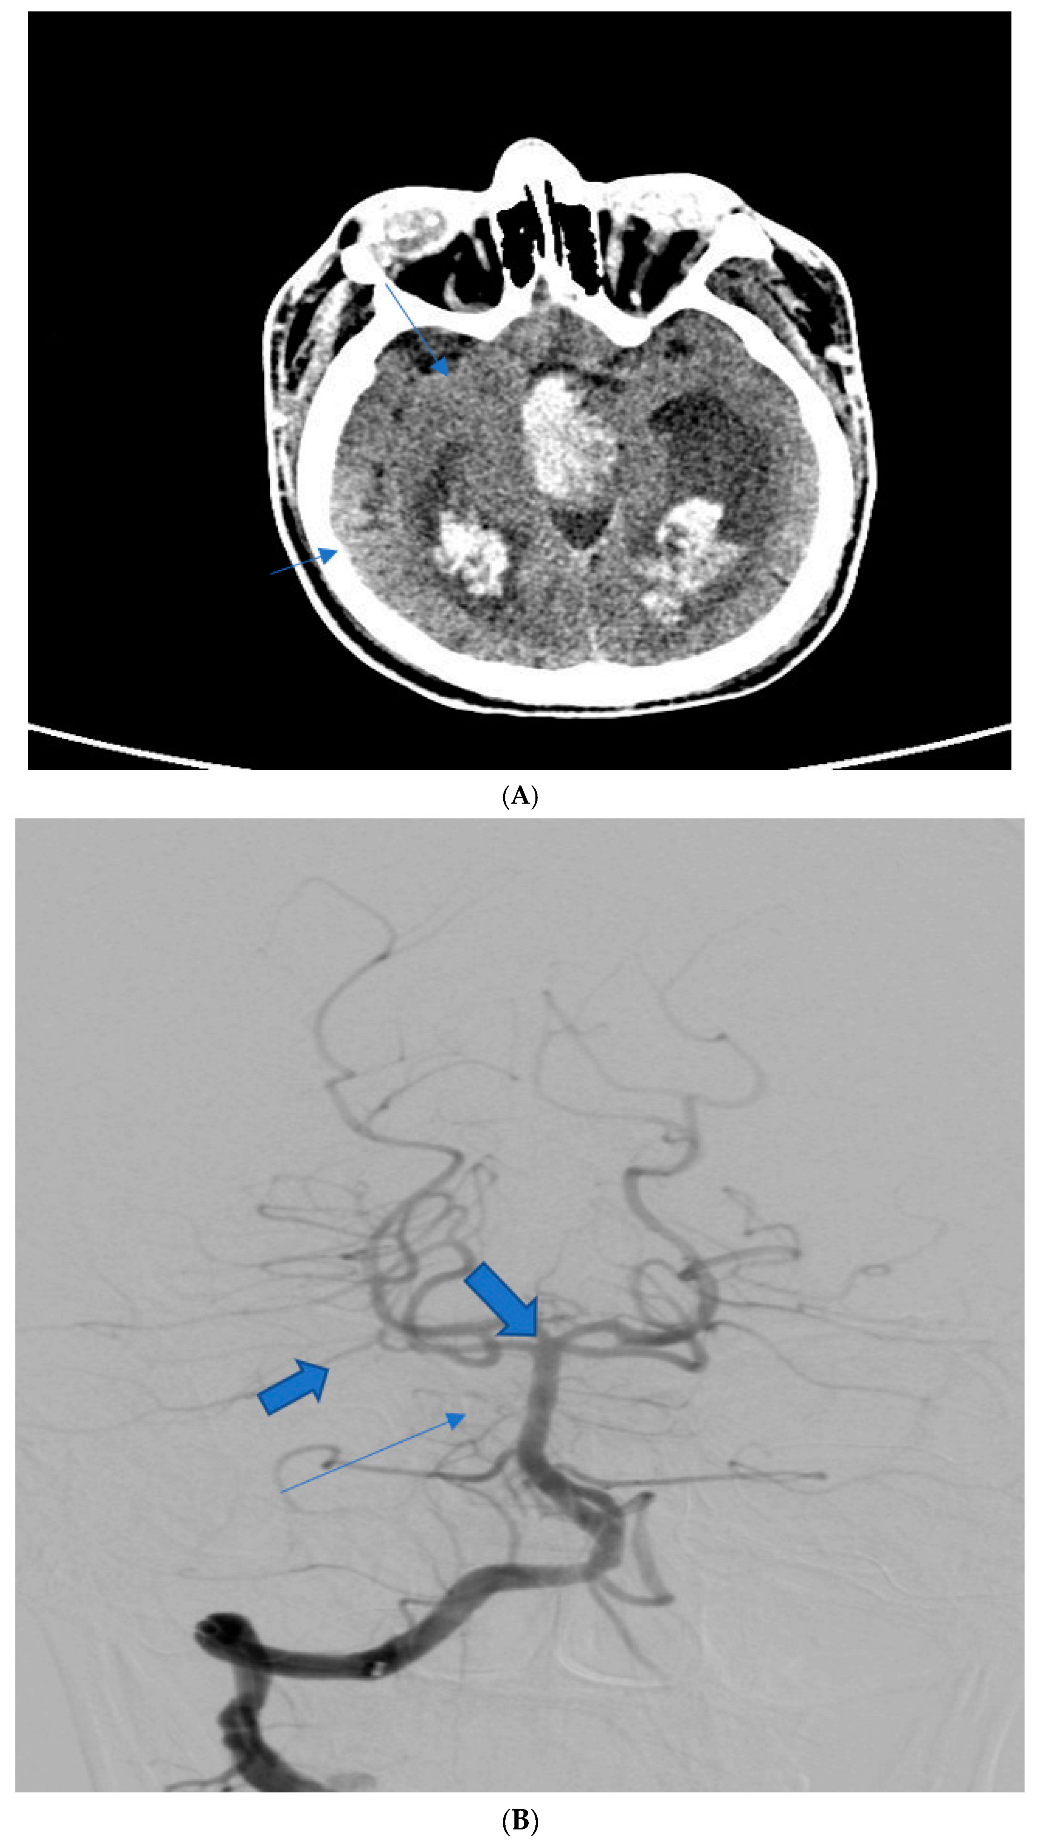

| 54 | F | Diplopia, headache | Native CT scan, CTA | I | I | Mild vasospasm, mild hydrocephaly | 2 | Nimodipine |

| 61 1 | M | Flaccid tetraplegia, altered Mental status | Native CT scan, DSA | IV | IV | Severe vasospasm, hydrocephalus | 6 (deceased) | Nimodipine, mannitol |

| 37 | M | Headache, diplopia | Native CT scan, DSA angiography | II | II | None | 3 | Nimodipine |

| 48 | F | 3rd nerve palsy, pupillary anomalies | Native CT scan, CTA | II | II | Mild vasospasm | 2 | Nimodipine |

| 41 2 | M | Headache, diplopia | Native CT scan, DSA | III | III | Mild vasospasm | 3 | Nimodipine, mannitol |

| 59 | M | 3rd nerve paresis, pupillary anomalies, hemiplegia | Native CT scan, DSA angiography | V | IV | Hydrocephalus, moderate vasospasm | 4 | Nimodipine, mannitol |

| 44 | F | Right internuclear ophthalmoplegia | Native CT scan, CTA | III | I | None | 1 | Nimodipine |